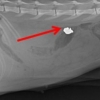

총상 입은 ‘동물농장 고양이’… ‘아찔’하게 박혀있는

총상 입은 ‘동물농장 고양이’… 누가 쐈을까 길고양이들이 많이 몰려 고양이 애호가들 사이에 명소가 된 지방의 한 관광휴게소에서 고양이…